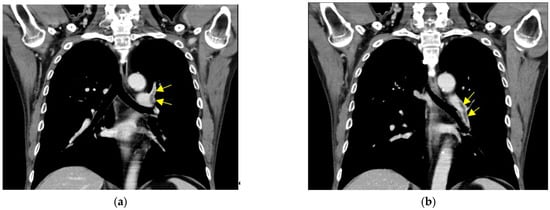

Computed Tomography (CT) of chest and extremities (Figure 1) showed left pulmonary artery thrombosis and right femoral vein thrombosis in the first case.

Figure 1.

CT of chest and extremity: (a,b) left pulmonary artery thrombosis; (c,d) right femoral vein thrombosis. Arrow indicates thrombosis.